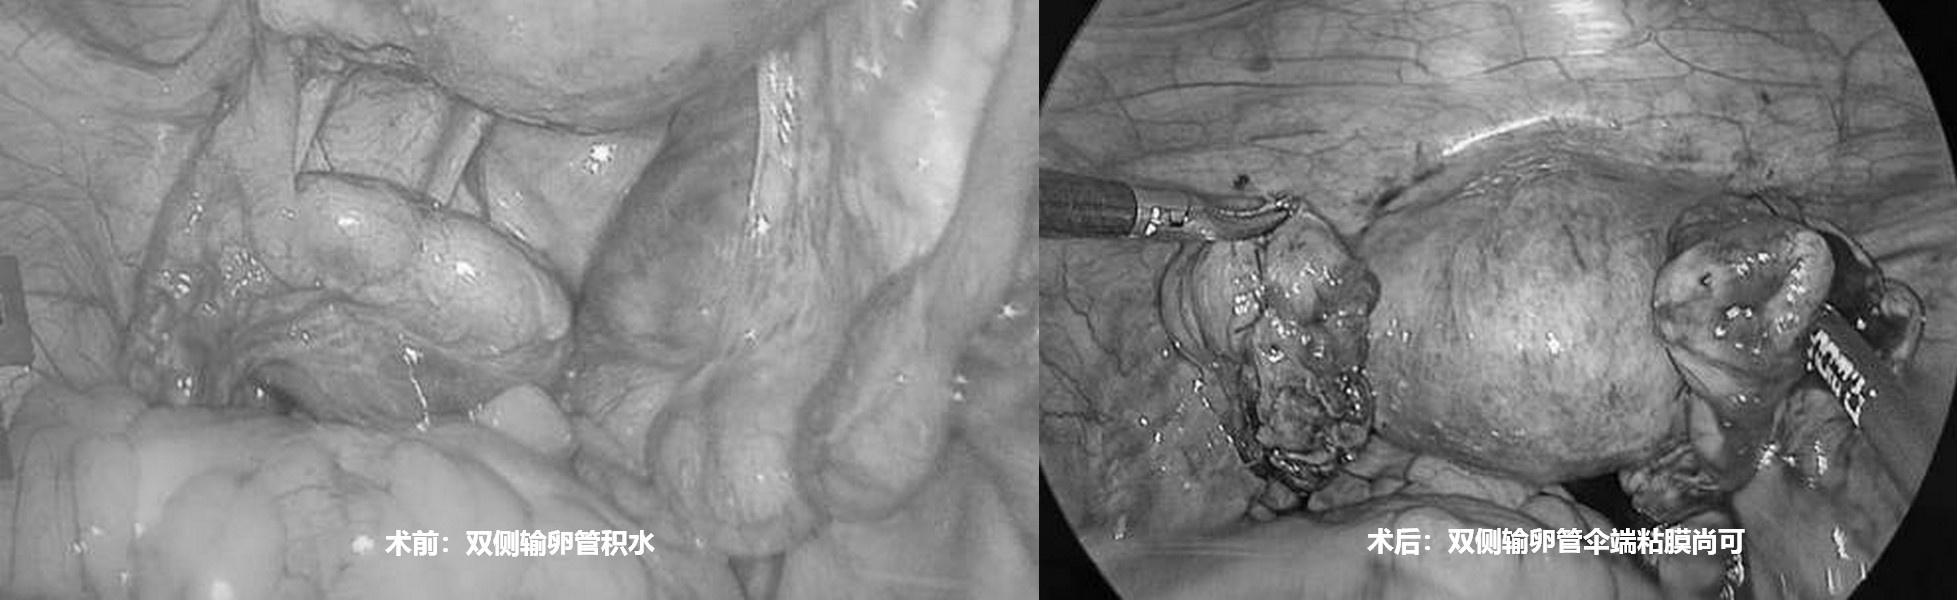

输卵管积水,想怀孕的最好方式是什么?